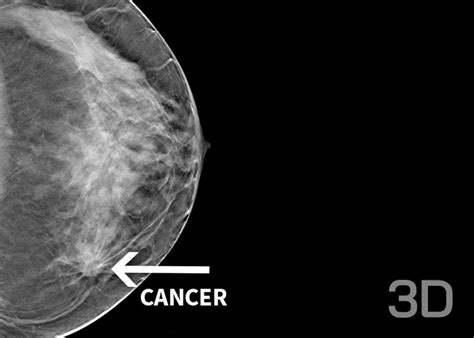

- Mamografie digitală 3D cu tomosinteză - esențială pentru depistarea precoce a cancerului de sân.

Cancerul de sân afectează una din opt femei de-a lungul vieții. Mamografia reprezintă investigația principală pentru screening, având rolul de a depista cancerul în stadii incipiente.